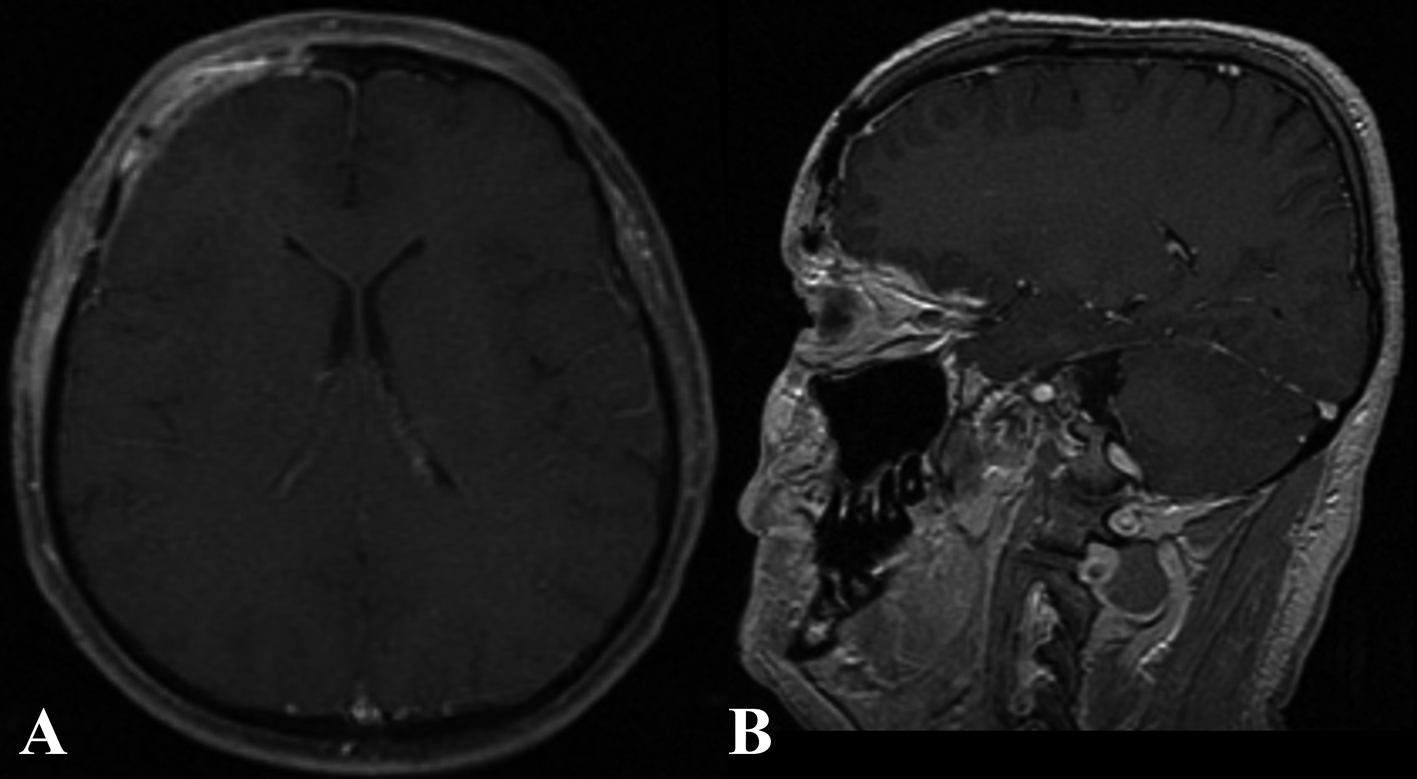

The patient’s postoperative course was uneventful. At 6 months follow up, the patient reported no more episodes of headache (Fig. 4, 5).

![]() Click for large image | Figure 5. Six months post-operative enhanced MR in the axial (A) and sagittal (B) plain. |